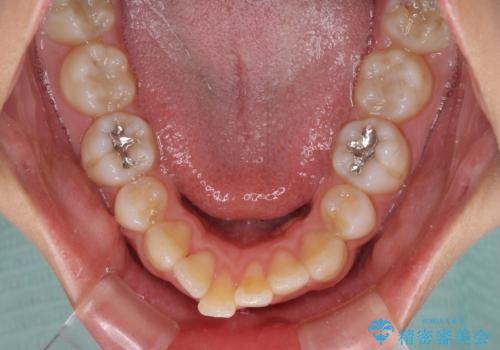

抜歯矯正の後戻り インビザライン・ライトによる矯正治療

- 矯正治療の後戻りを気にして来院された患者様です。

後戻りは軽微であったので、インビザライン・ライトにより矯正治療を行うこととしました。

治療途中、妊娠・出産があり、1年近く治療が停滞しましたが、無事に終了することができました。